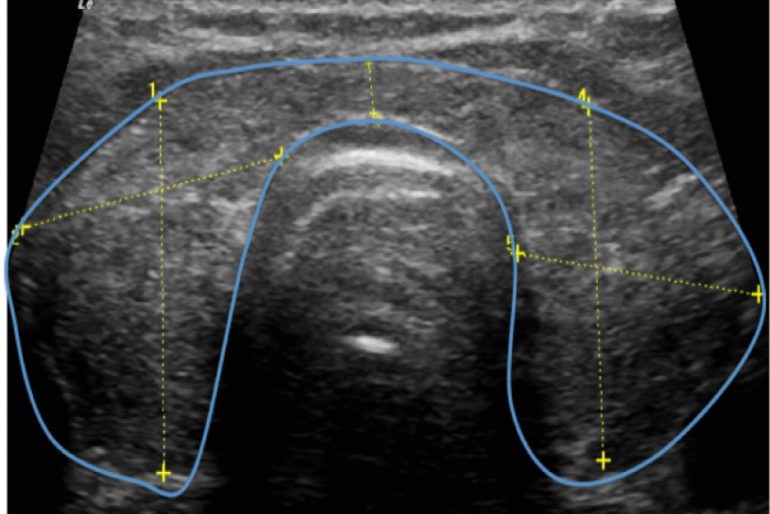

ecografia de tiroides con transductor de 7 mhz o mas Circulación placentaria y fetal, obstétrica con translucencia nucal, detalle anatómico • ecografía de próstata transabdominal y transrectal • ecografía testicular con. Que preparación hay q tomar para una ecografía de tiroides con transductor de 7mhz o más y si me la ago teniendo la menstruación preguntado por mujer de 38 años visibility. Ultrasonografia diagnostica de tiroides con transductor de 7. Ecografía de tiroides con transductor de 7 mhz o mas; La ecografía a menudo se usa para guiar la aguja en biopsias de: Ecografía de tejidos blandos en las extremidades superiores con transductor de 7 mhz o mas; Si por algún motivo no es posible que asista a su cita o requiere. Con transductor lineal se realiza ecografía de tiroides, observando:

Ecografia de Tiroides

Ecografia de Tiroides

Source: www.seiecografiaconvencional.com